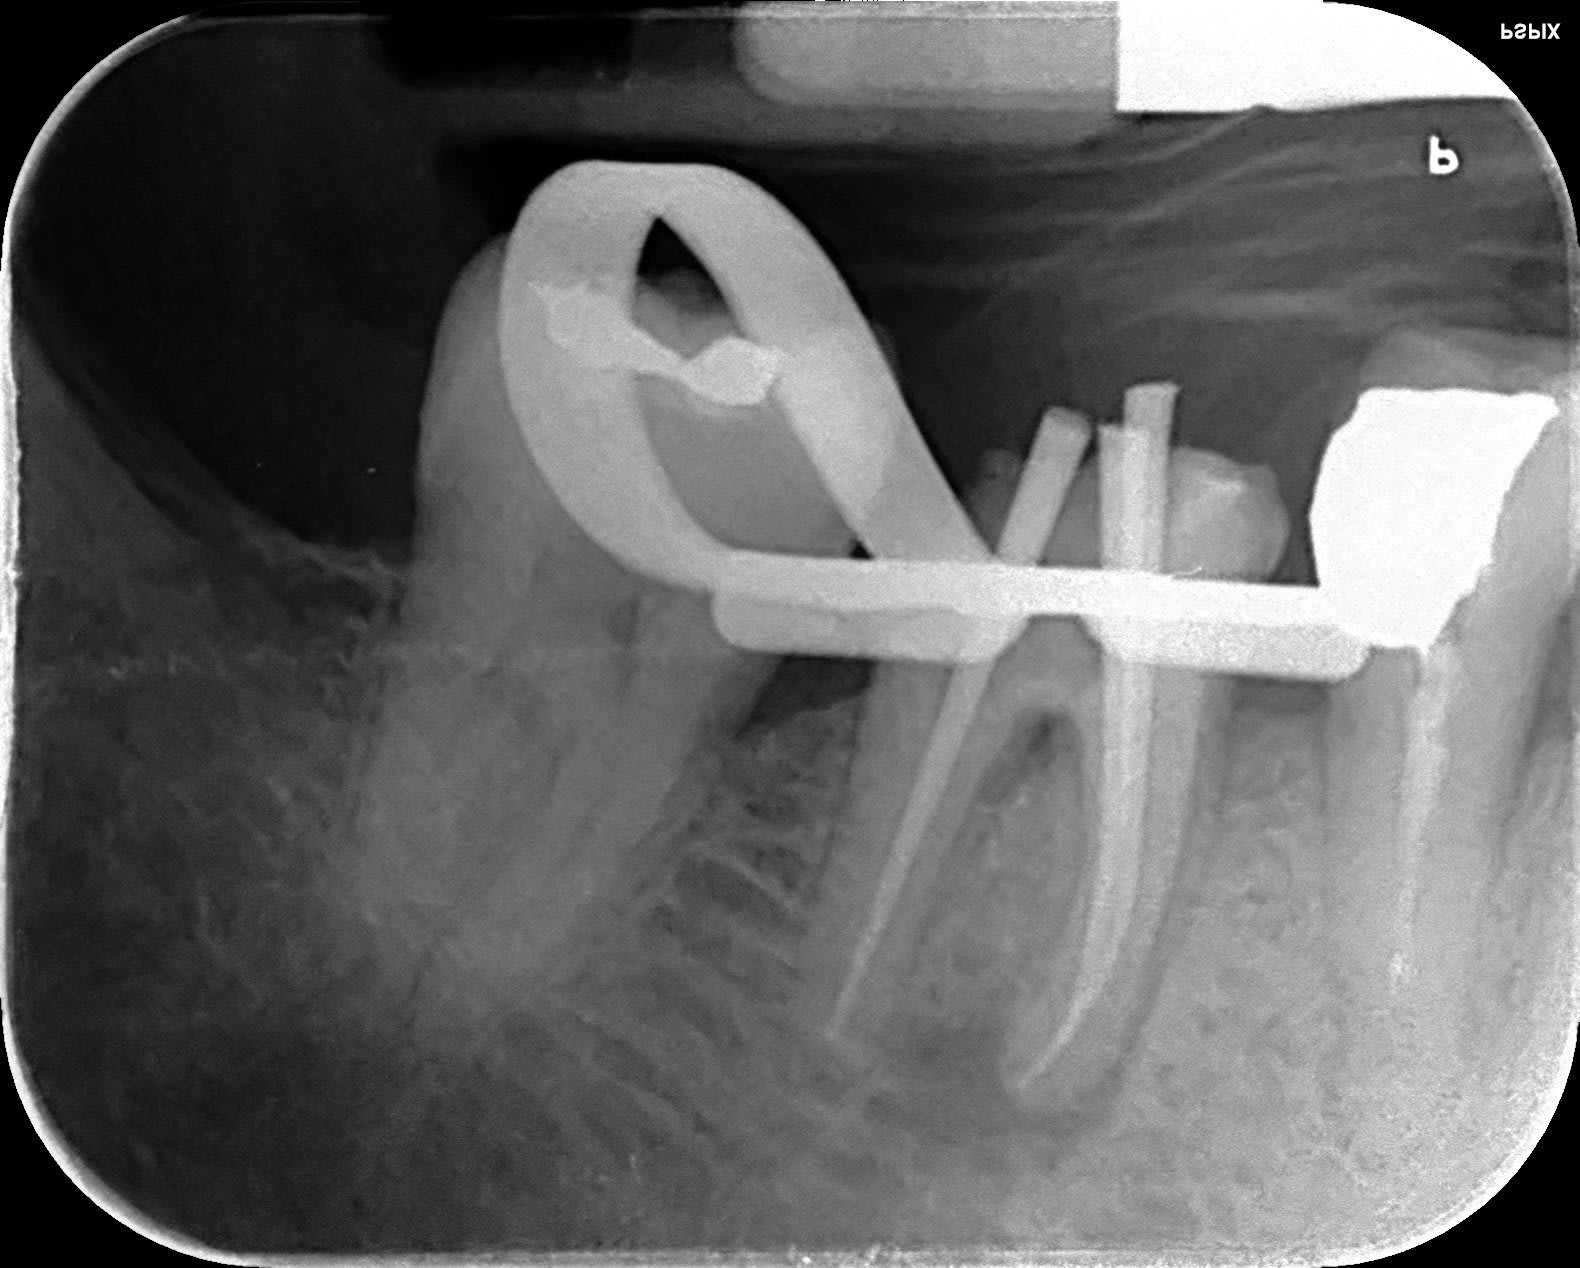

Faite avec des PTU et du temps (argentique... :-( c'était il y a loin) je ne suis pas certain d'avoir le même résultat avec des r25, je ne m'y risquerai pas.

Dscf2279 li 2 zq1fbe - Eugenol

Dscf2280 cybwak - Eugenol

He! Dante!! Tu sais le faire ça? ;-)) le "fragment" fracturé, je l'ai retiré, c'est pas si simple parce que ça visse.